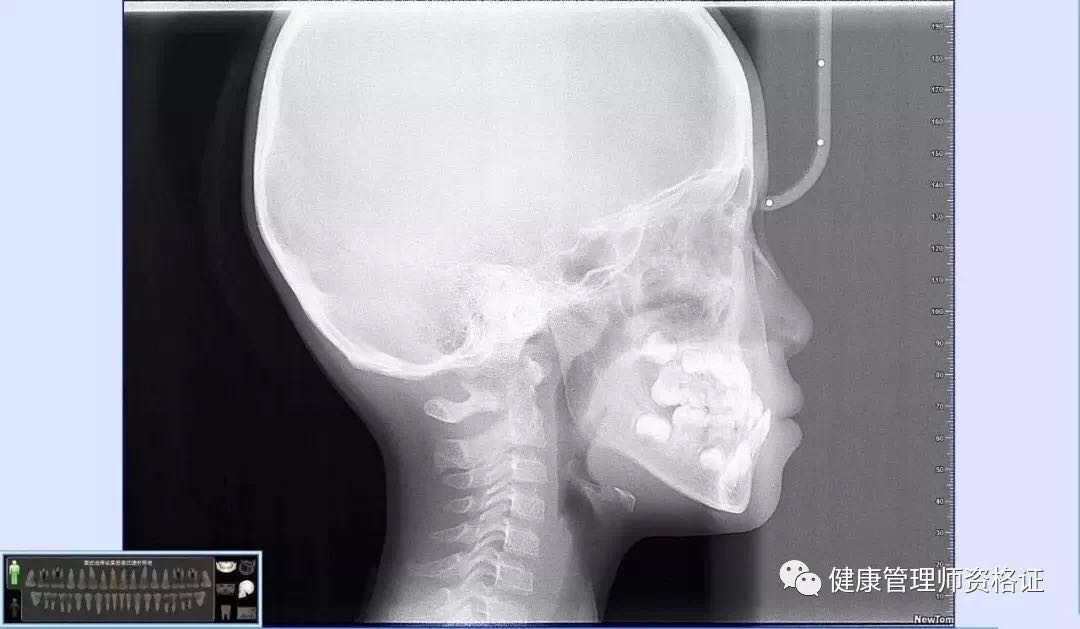

(2) 牙科頭顱側位片

可以展現牙齒及頜骨影像。可見孩子側面骨骼、上下頜骨發育 、氣道、腺樣體等各組織結構間是否影響孩子面型發育。